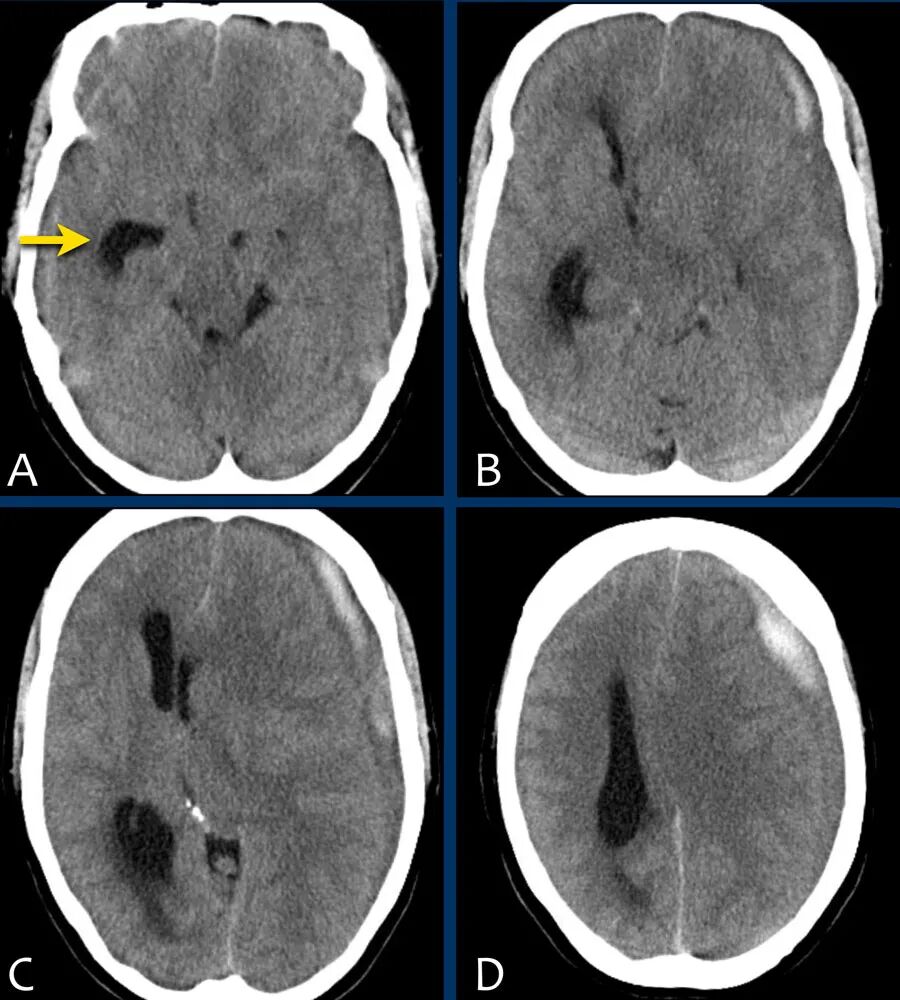

下图显示硬膜下血肿。

注意血肿有高密度区和等密度区。

这可以在超急性出血中看到,但也可以在再出血中看到。

中线结构移位,脑脊液血流受阻,导致右侧脑室颞角扩张(箭头)。

急性硬膜下血肿为高密度(凝血),亚急性血肿为等密度,慢性硬膜下血肿表现为低密度(同脑脊液)。

活动性出血征象:

在急性情况下,硬膜下血肿可能出现异质性:新鲜的非凝血(低)和凝血(高)。